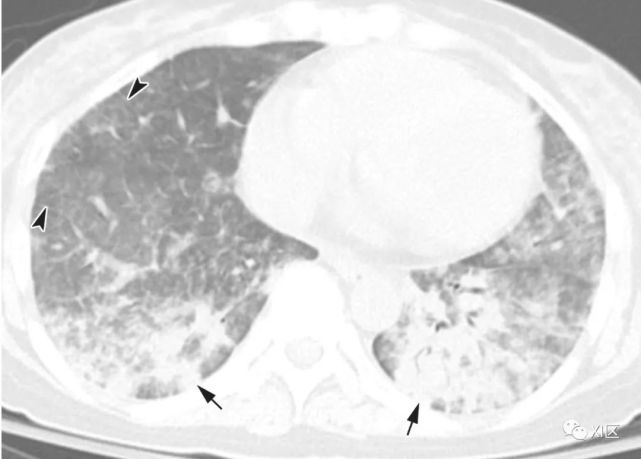

图7 甲型流感病毒引起的肺炎表现为沿支气管血管束的多个不规则的实变区(箭)和弥漫性GGO(箭头),两肺小叶间隔增厚。

图7 由鼻病毒引起的肺炎显示多个边界不清的GGO斑片状区域(箭),两肺小叶间隔增厚(箭头)。

图示为典型的病毒性肺炎的CT表现。